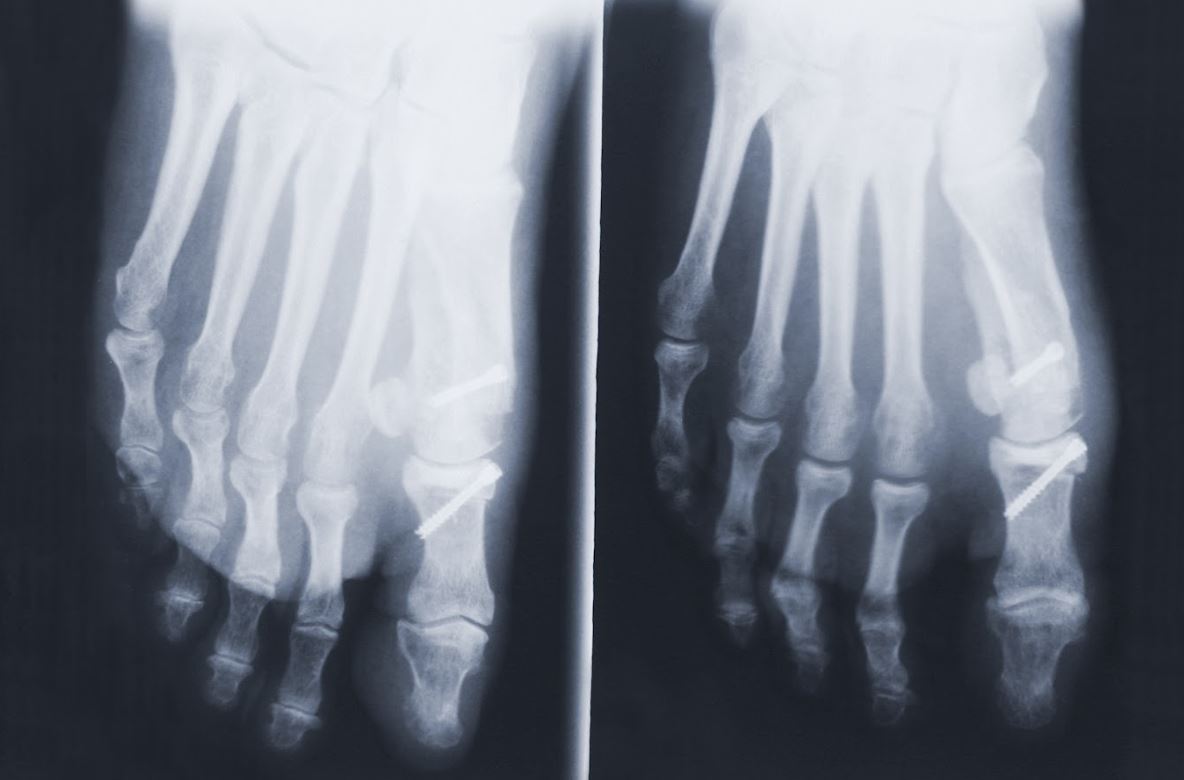

Types Of Big Toe Surgery . The corrective surgery for bunion is known as a metatarsal osteotomy or bunionectomy. The procedure involves an incision in the skin and removal of excess bone with the aid of orthopedic tools that cut away the bone spurs. A first mtp joint fusion is a surgical procedure to treat arthritis of the big toe. Big toe arthritis (also known as hallux rigidus) can cause pain and swelling and lead to difficulty. A keller’s arthroplasty is a surgical procedure to remove bone from the spot where your big toe joint meets the metatarsal bone and replace it with soft tissue. There are four main types of bunion surgery: This procedure is often done. There are multiple techniques, but all involve cutting the bones and repositioning. A cheilectomy is a surgical procedure to remove excess bone from the joint of your big toe, also called the dorsal metatarsal head. Cheilectomy is an operation of the metatarsophalangeal (mtp) joint, where the big toe bends and attaches to the foot. Toe joint replacement is surgery to remove a damaged toe joint and replace it with an artificial (manmade) joint. Your surgeon will make a few small incisions (cuts) in your foot and toe bones.

A keller’s arthroplasty is a surgical procedure to remove bone from the spot where your big toe joint meets the metatarsal bone and replace it with soft tissue. There are four main types of bunion surgery: Big toe arthritis (also known as hallux rigidus) can cause pain and swelling and lead to difficulty. Your surgeon will make a few small incisions (cuts) in your foot and toe bones. A cheilectomy is a surgical procedure to remove excess bone from the joint of your big toe, also called the dorsal metatarsal head. There are multiple techniques, but all involve cutting the bones and repositioning. Toe joint replacement is surgery to remove a damaged toe joint and replace it with an artificial (manmade) joint. Cheilectomy is an operation of the metatarsophalangeal (mtp) joint, where the big toe bends and attaches to the foot. The corrective surgery for bunion is known as a metatarsal osteotomy or bunionectomy. The procedure involves an incision in the skin and removal of excess bone with the aid of orthopedic tools that cut away the bone spurs.